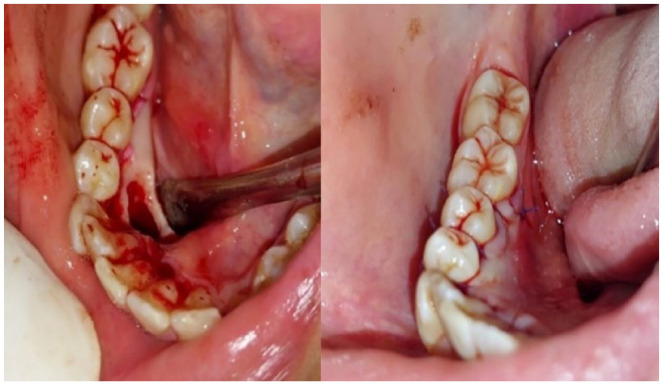

Calcifying odontogenic cyst, also known as Gorlin cyst is a rare benign cystic lesion primarily found in the jawbones, accounting less than 1% of odontogenic cysts. It can be associated with odontogenic tumors such as odontomas. We report a rare case of COC associated with complex odontoma in a young patient and discuss its clinical features, diagnosis, and treatment options. An 18-year-old female patient presented with a painless radiopaque lesion of the right mandibular bone at Oral Medicine and Oral Surgery department. Radiographs revealed irregular tooth-like structures in the canine-premolar area. The lesion was surgically removed, and histopathology confirmed COC with a complex odontoma. As of the World Health Organization's 2022 definition, COC is a developmental odontogenic cyst characterized by calcified ghost cells. It typically affects individuals during their second and third decades of life, with no gender preference, almost equally in the maxilla and the mandible. The main treatment is total enucleation, with a generally favorable prognosis. Histopathology is essential for diagnosis due to its mimicry of other jaw conditions. Long-term follow-up is needed to prevent recurrences.

Abstract Image